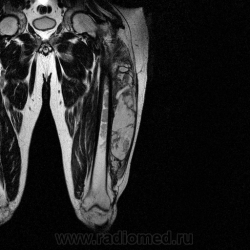

Добрый вечер Татьяна Валентиновна, можно и МРТ, а можно и результат гистологии, все по порядку, сейчас МРТ продемонстрирую.

Ну вот аксиальные срезы, где то затерял =(

С учетом вашего опыта, мне кажется Вам и без дословной интерпретации МР-протокола будет все понятно.

Мой коллега в заключении указал о вероятней всего рабдолейомиосаркоме, если я ошибся то чуть позже поправлюсь.

Я тоже пока что в этом деле лось, но думаю дело поправимое, на днях улетаю С-Петербуг в МАПО(цикл КТ и МРТ), ну да ладно, что косается пациента то он ещё в 2007 году обращался по месту жительства к травматологу по поводу ушиба бедра с формированием гематомы, была назначена местная рассасывающая терапия, до 2009г. видимо ждали пока рассасется в декабре обратился к хирургу по поводу посинения и увеличения в объёме задней поверхности бедра, назначен гепарин в феврале был вскрыт абсцесс в этом месте, далее только в марте сподхватились по УЗИ-мягких тканей признаки образования, ну и открытая ножевая биопсия: Описание изменений, выявленных при микроскопическом исследовании: в материале фрагменты опухоли, представленной пучками вытянутых клеток с полиморфными гиперхромными, местами уродливыми ядрами. Определяется значительное количество митозов, встречаются поля некроза опухоли. При иммуногистохимическом исследовании опухолевые клетки экспрессируют виментин, отсутствует реакция на десмин, гладко-мышечный актин, S100. Патоморфологическое заключение: саркома мягких тканей, боее вероятно фибросаркома.